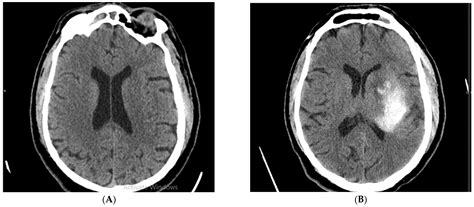

Computed Tomography (CT) scans are essential in the diagnosis of ischemic stroke. An Ischemic Stroke CT scan can quickly and accurately detect the presence of a stroke, differentiate it from other conditions, and guide treatment decisions. The scan uses X-rays to create detailed images of the brain, which can reveal:

• Hemorrhage: Whether the stroke is ischemic or hemorrhagic, which is crucial for determining the appropriate treatment.

• Non-contrast CT (NCCT): This is the most basic type of CT scan and is often the first test performed. It provides a clear view of the brain structures and can detect early signs of ischemia, such as the “dense artery sign,” which indicates a blood clot.

Interpreting the results of an Ischemic Stroke CT scan requires expertise and experience. Radiologists and neurologists work together to analyze the images and make a diagnosis. Key findings that may be observed include:

• Early ischemic changes: These can appear as areas of low density (hypodensity) in the brain tissue, indicating reduced blood flow.

• Hyperdense artery sign: This is a bright appearance of an artery on a non-contrast CT scan, suggesting the presence of a blood clot.

• Mass effect: Swelling or compression of brain tissue due to the stroke, which can be seen as a shift in the midline structures of the brain.